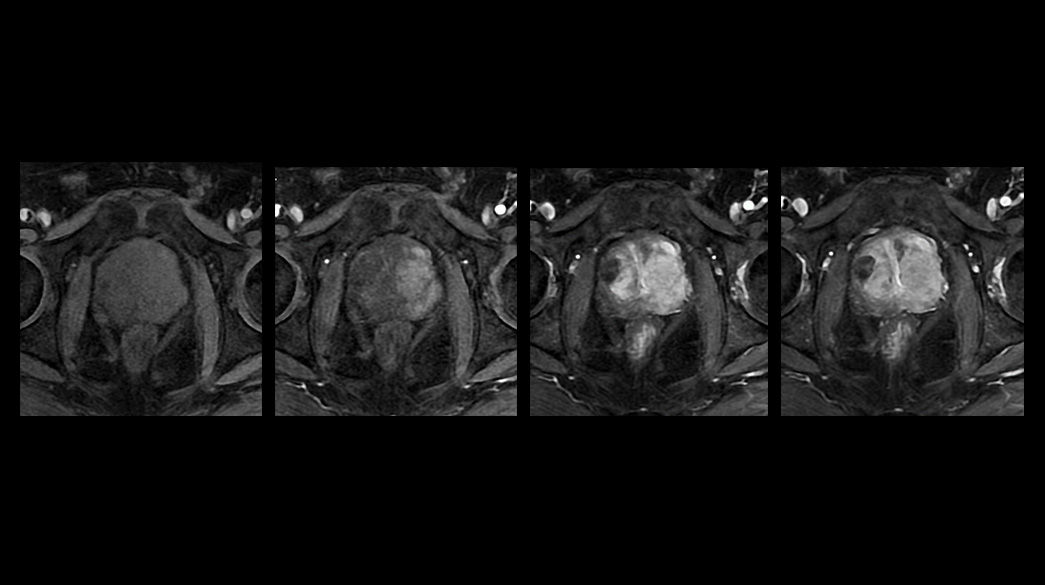

Precision and personalization

Advanced-DWI1040-x-585

Read case study ico-caret-right